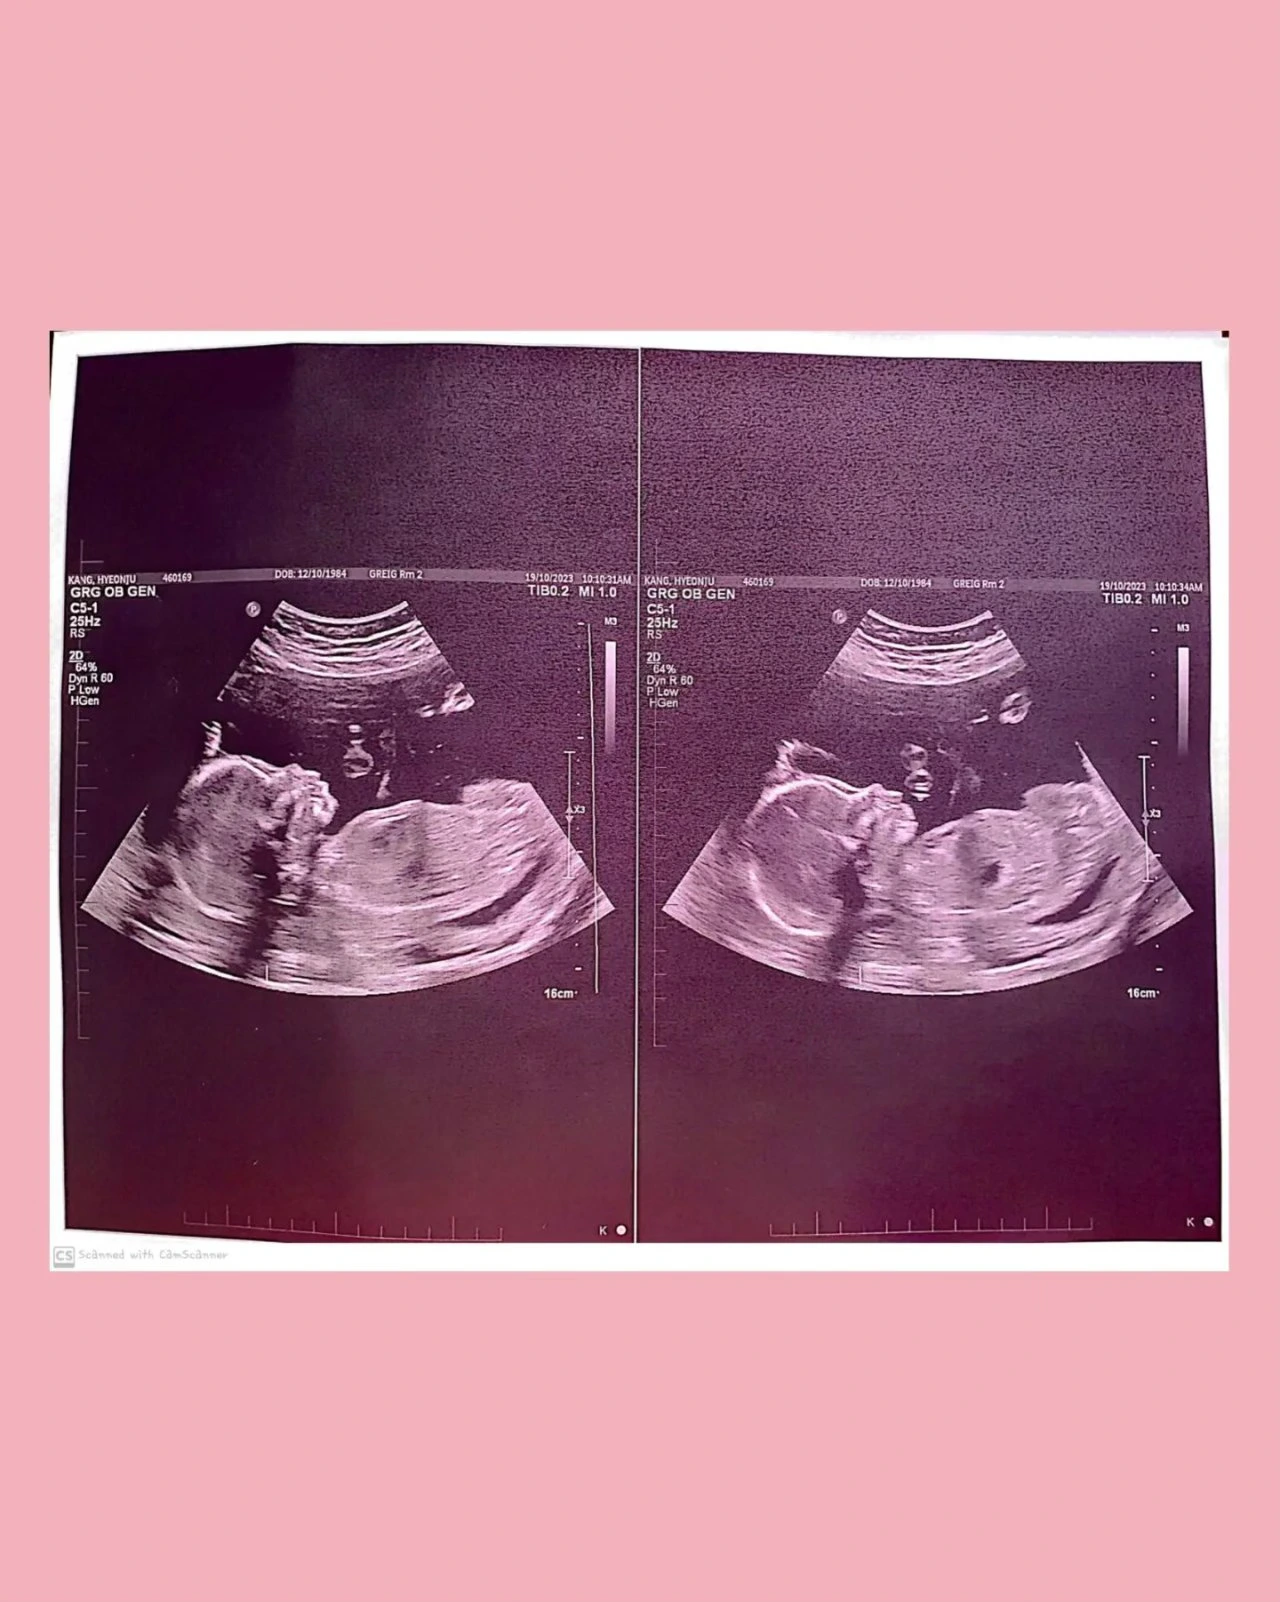

선생님께서 초음파기를 갖다 대니 우주는 이리저리 움직이면서 오랜만에 다가온 새로운 감각에 반응을 하기 시작했다. 배 가운데부터 시작해서, 위아래 오른쪽 왼쪽 등 여러 방향으로 몸을 움직이면서 우주의 얼굴이나 손 그리고 발까지 아기의 몸상태가 양호한 지 혹은 이상이 있는지 세심히 잡아주셨다. 거기에 맞춰서 잡기 놀이 라도 하는 듯 우주는 요리조리 피하기 바빴고 가만히 있으면서 차분히 도와주기도 했다.

차분히 사진들을 정리해서 보여주시면서, 손가락과 발가락 개수도 정확하고 매우 활동적이면서 유연한 몸을 가지고 있는 건강한 ‘딸’이라고 말씀해 주셨다.